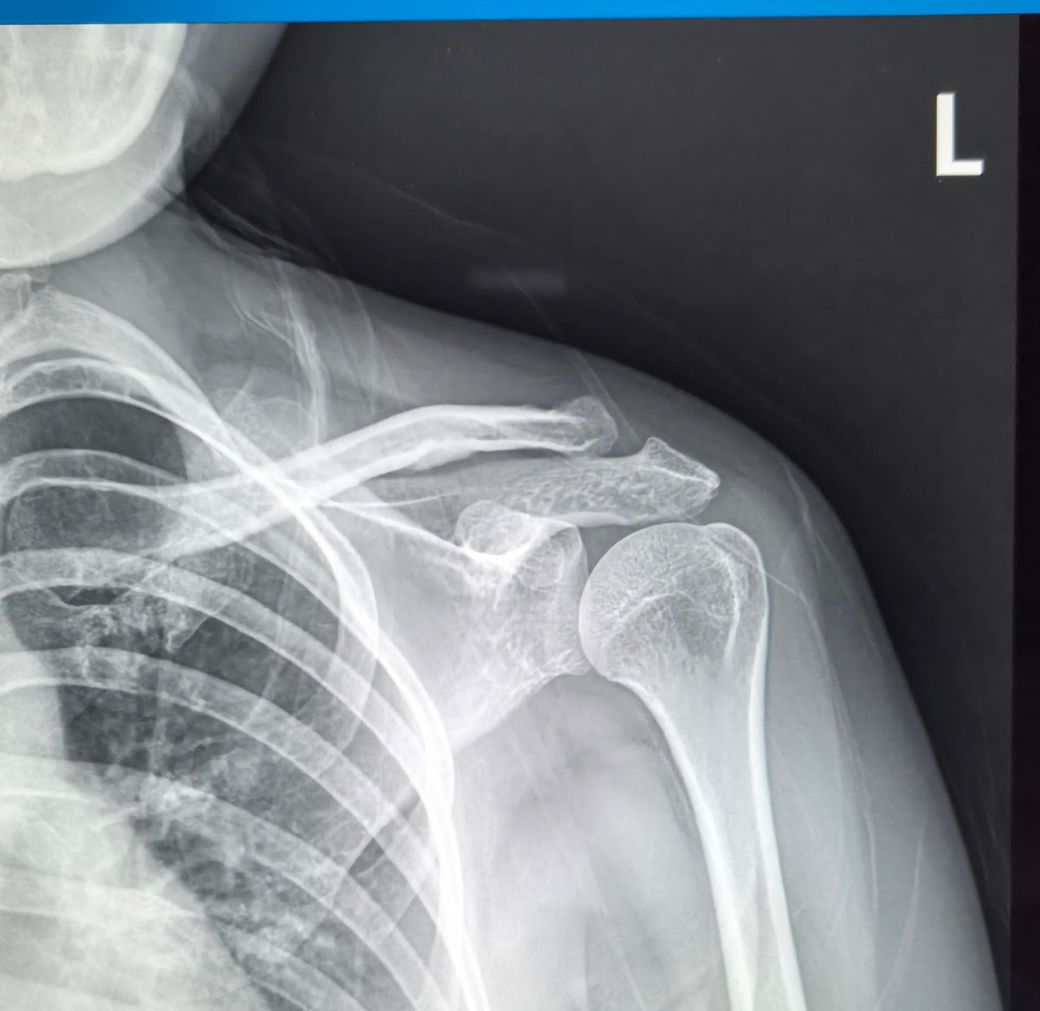

어께 골절 어때보이나요?심해보이나요?

어께뼈 사진인데 왼쪽이 골절됬다가 다시붙었다는데 골절이 된건가요? 붙은건가요?

골절이된거면 병원을 다시 가봐야하나요??

• 1번 째 사진

사진상으로볼때에는 골절부분을 확인하는게 어려운데요 병원에서 골절을 진단받았을당시에 엑스레이사진을 보여주셔야 확인이가능합니다~

우선 현재로썬 전문의에 소견이 골절이 됐다가 유합이 됐다는 소견이 있기에 현재로썬 골절 부위는 확인을 하기 어렵습니다.

전문의에게 어디가 골절 부위였는지 안내 받으시고 만약 통증, 움직임 제한, 불편감이 있다면 병원에 내원하시길 바랍니다^^

검사이후에 골절이 발생했었다는 소견을 제외하고 특별한 이상소견을 들으신 것이 아니라면 문제가 될 가능성은 낮습니다.

어깨부위에 통증이나 불편감이 있다면 다시 진료를 받아보시고 그에관한 치료를 고려해보시는 것을 추천드립니다.